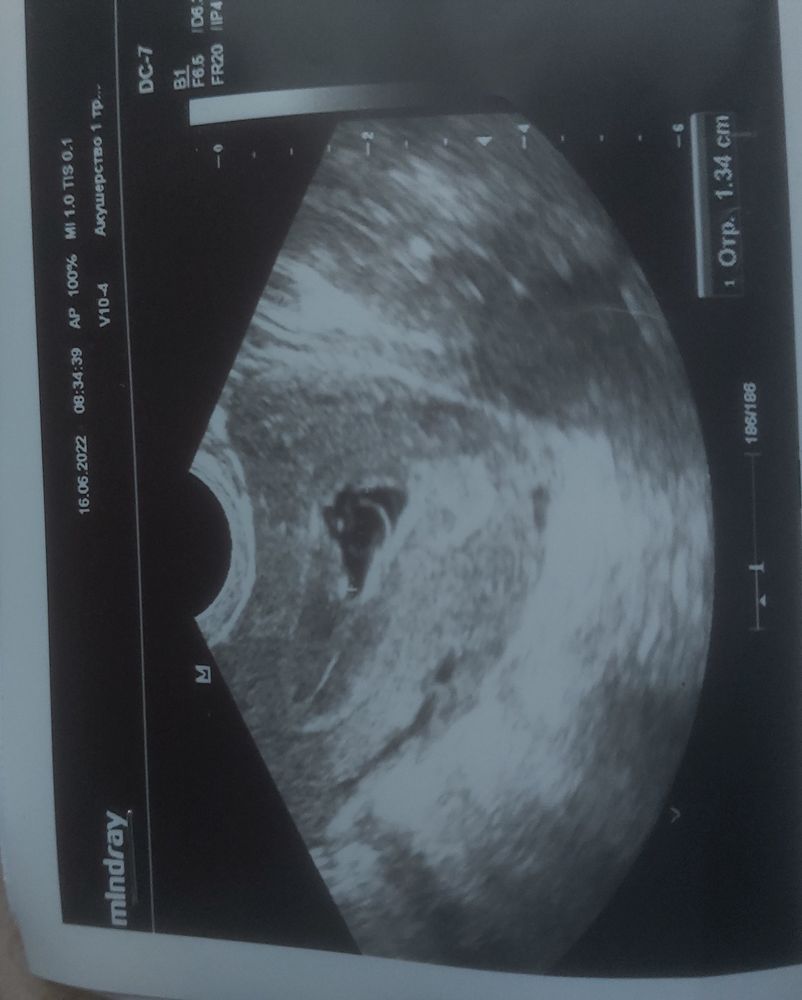

Доброго времени суток,Это первое узи, есть ли шанс? Или нет? 5 недель 6 дней

От тонуса сплющило плодное яйцо,а для эмбриона рано. Правильно пишут: магний б6 и спокойствие. УЗИ чере неделю, две

А какого размера жм у вас? По фото кажется большое

Марина, мне вообще сказали что жм нету

Dana, как нету,у вас кружок большой в пя

Виктория, мне сказали что плод должен быть круглым

Dana, ещё слишком маленький срок. Может примет нормальную форму. Сделайте узи через неделю

Гузель, мне сказали что плод должен быть круглым и не виден эмбрион

Dana, а вы не нервничали? мне когда сказали что ПЯ не правильной формы, я прочитала тут что делать и пила магне В6 по 2т 3р в день, через два дня плодное яйцо было правильной формы. Эмбрион у меня тоже увидели только в 6н2д у кого то в 8 недель только находят. Не переживайте, сделайте узи в динамике через 2 недели

Dana, больше спокойствия, можете пропить магне В6, он не противопоказан беременным, наоборот успокаивает тонус, нервы, с ними я спокойнее стала😁 Удачи 🍀 пусть всё будет хорошо, а шансы есть🥰